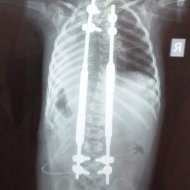

Farklı tipte skolyozu olan hastaların ameliyat öncesi ve sonrası fotoları: